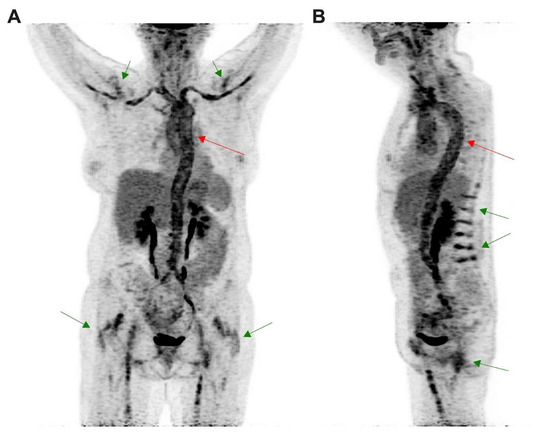

[18F]FDG PET/CT Imaging in Large Vessel Vasculitis